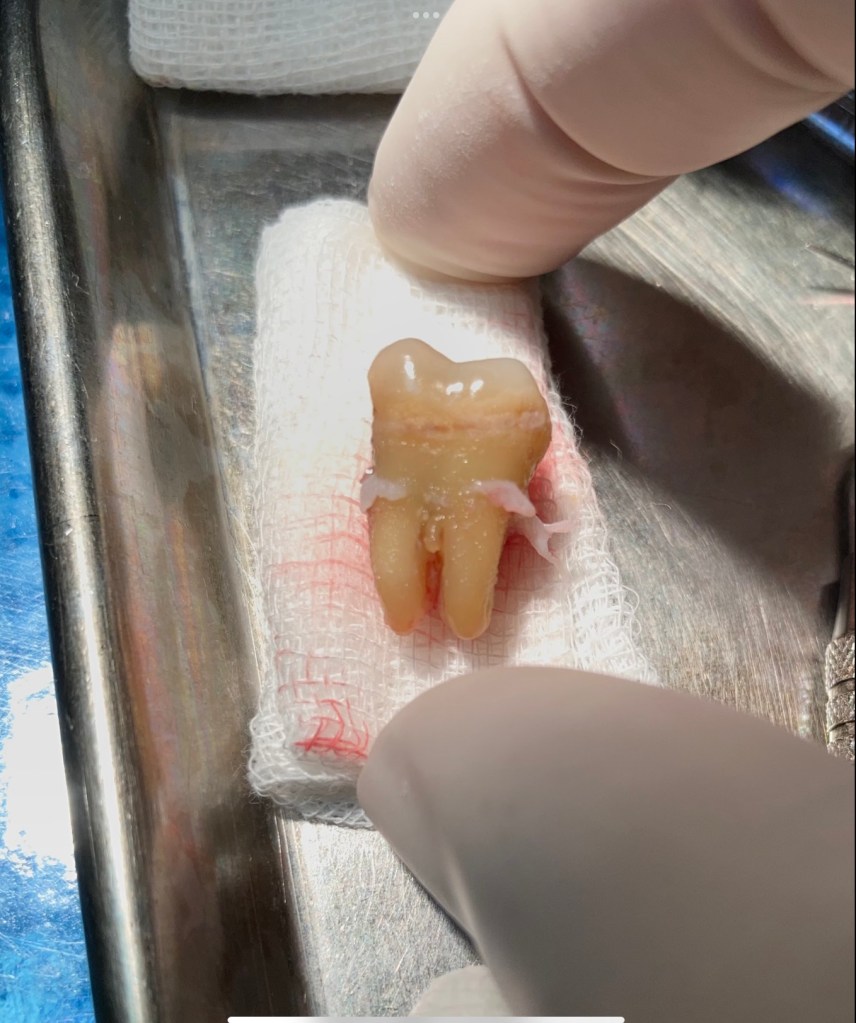

Don’t Remove. (before X-ray) radix-ento พบได้ในคนไทย 12.7% Germination X-ray ช่วยให้เห็นสิ่งที่ซ่อนอยู่ภายใน สังเกต furcation ก็รู้ว่าฟัน Perio Mermaid Premolar ให้สังเกตที่ mouth mirror เห็นถึงความฝ้ามัว เป็น Br พม่าครับ alloy ไม่แข็งมาก X-ray เท่านั้นจึงจะรื้อได้ ผมจะชอบวัดความยาวของฟันบ่อยๆ เทียบกับความยาวในใจที่เดาเอาไว้ RCT incomplete ใครสังเกตเห็นความผิดปกติบ้างครับ? ถึงกับต้องถ่ายทุกมุมเลยซี่นี้ remove ฟัน Crowding เป็น PVC ล้อมด้วยฟัน RCT อย่าลืม X-ray ก่อนถอนนะครับ Share this: Share on X (Opens in new window) X Share on Facebook (Opens in new window) Facebook Like Loading... Uncategorized